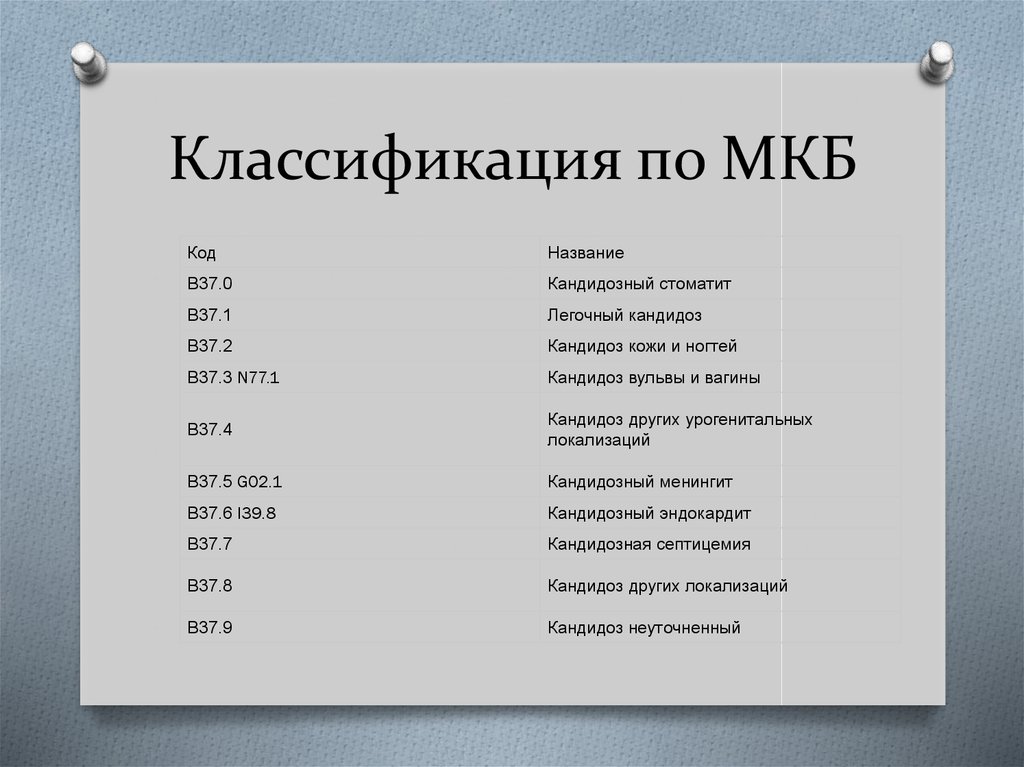

Код мкб 10 атерома головы

Код мкб 10 атерома головы 109 фото